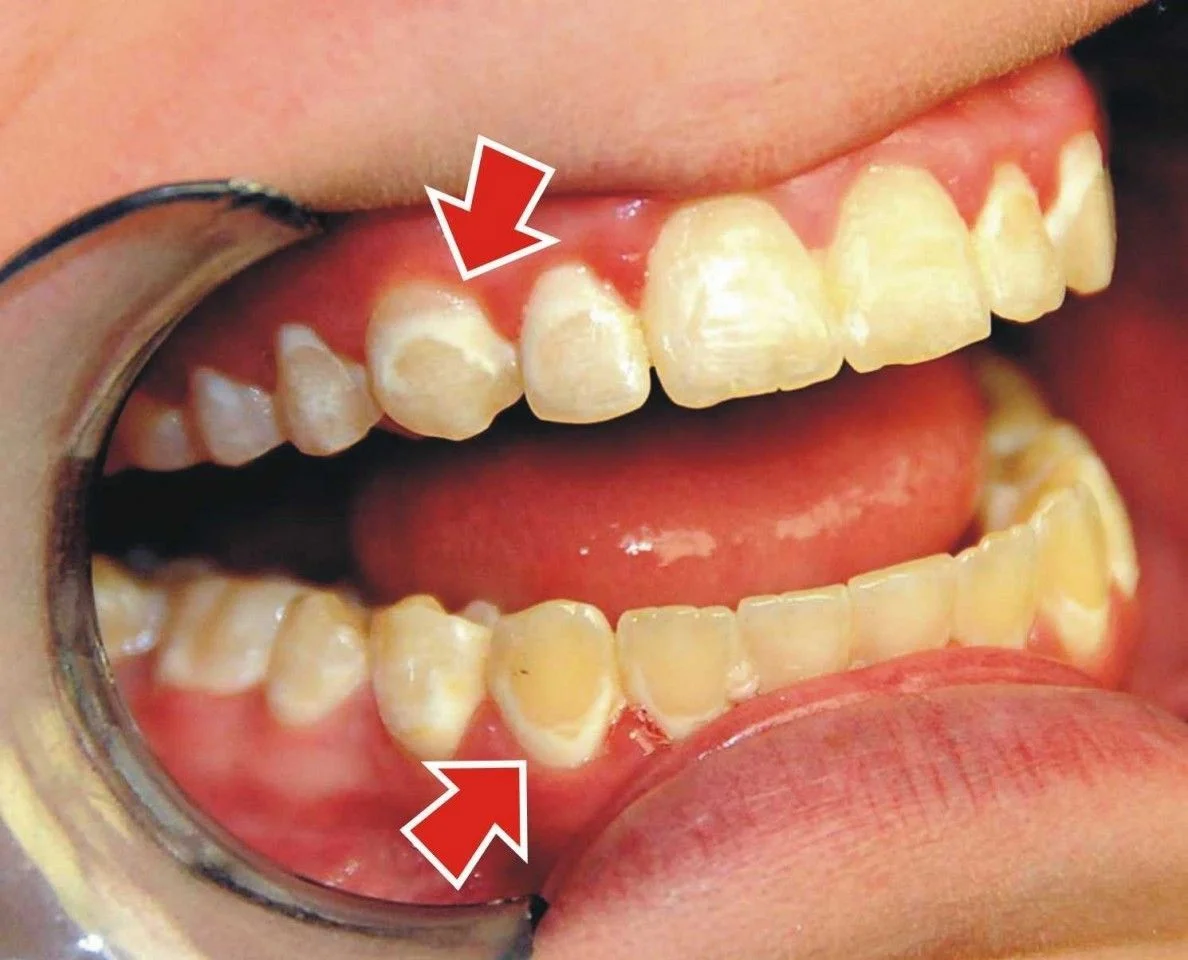

فلوئوروزیس دندانی به سه شکل خفیف، متوسط و شدید ظاهر میشود. علائم بسته به شدت فلوروزیس متفاوت است:

- فلوئوروزیس خفیف؛ معمولاً به صورت لکههای سفید روی دندانها ظاهر میشود. این لکهها ممکن است تنها بر روی سطوح بخصوصی از دندانها دیده شوند.

- فلوئوروزیس متوسط؛ علاوه بر لکههای سفید، ممکن است لکههای قهوهای کوچک نیز مشاهده شوند. سطوح دندانها ممکن است ناهموار شوند.

- فلوئوروزیس شدید هم شامل لکههای سفید بزرگ و لکههای قهوهای تیرهتر است. در موارد شدیدتر، ساختار دندانها ممکن است دچار خرابی شود و خطوط و ترکهای قابل مشاهدهای بر روی دندانها به وجود آید.